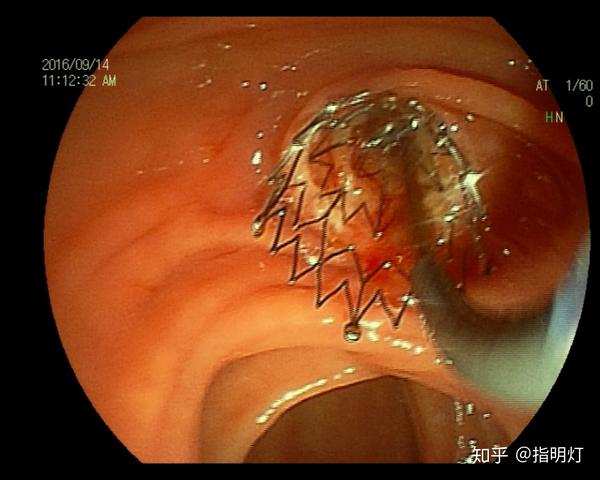

十二指肠溃疡

十二指肠溃疡的症状